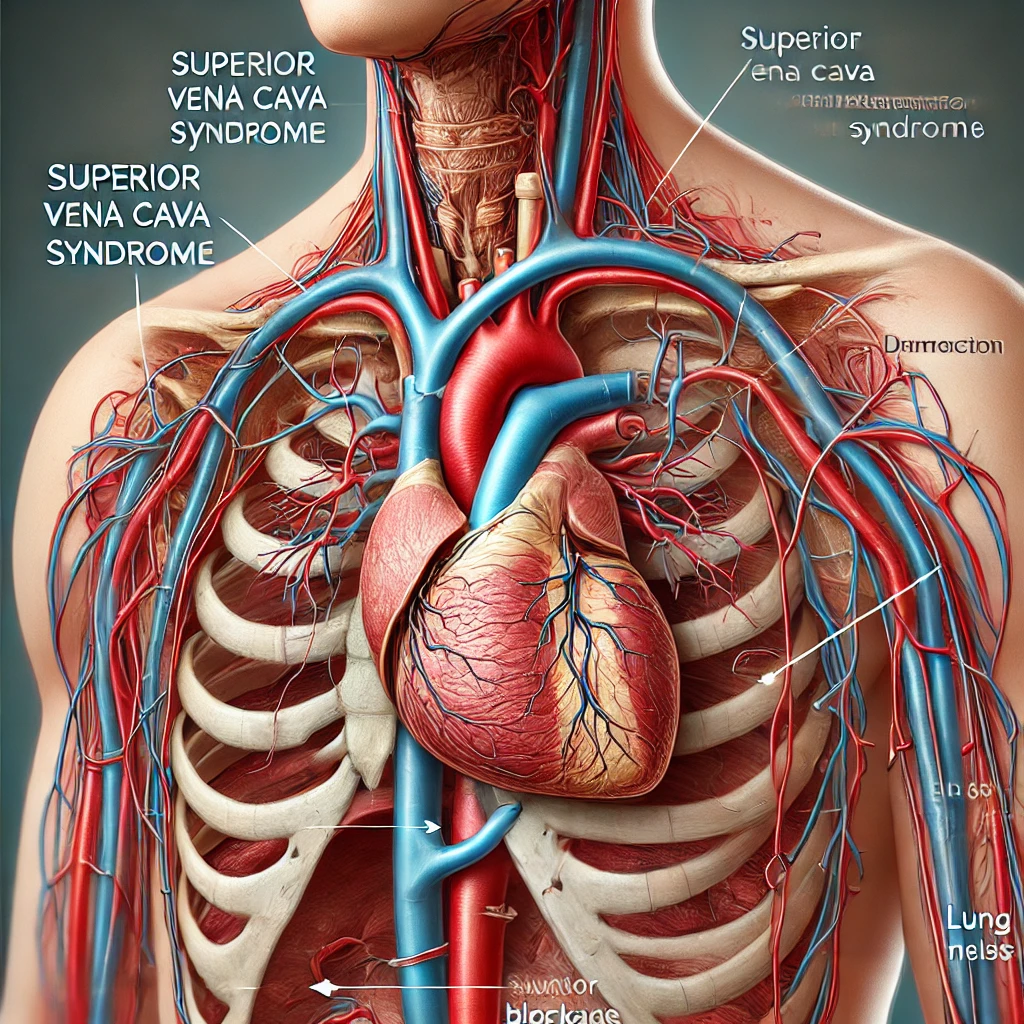

مقالات طبية من مساهمات الأطباء